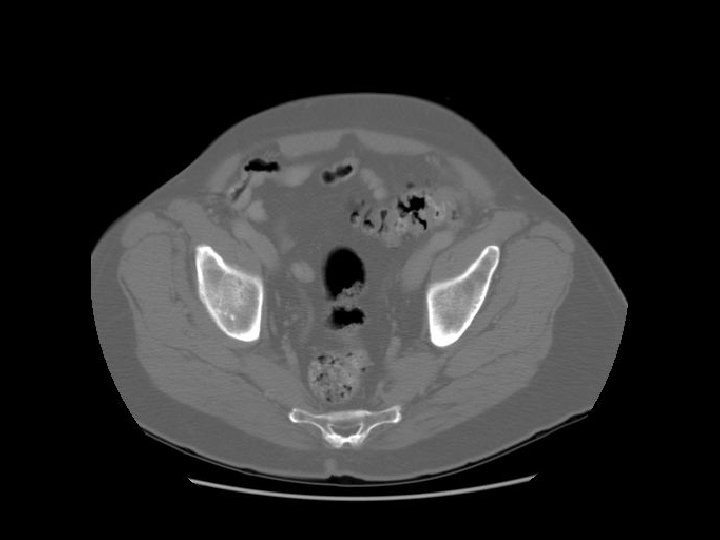

Bladder Prostate Rectum

Femoral head Acetabulum

Feces in the rectum

Pubic symphysis